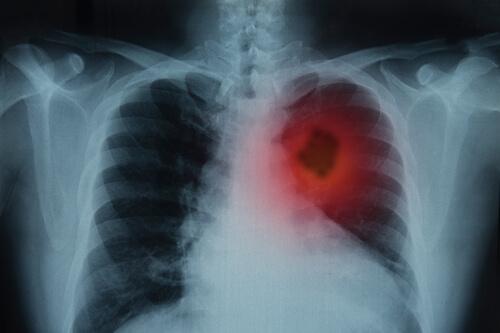

Akciğer Kanseri: Belirtileri Ve Tedavisi

Akciğerleriniz solunum sisteminizin en önemli bölümlerindendir. Burnunuza ve ağzınıza giren hava trake borusundan bronşlarınıza oradan da son olarak ciğerlerinize ulaşana kadar ilerler. Akciğer kanseri belirtileri ölümcül olabilir. Bu yüzden erken dönemde fark etmek önemlidir.

Ayrıca, belirtiler 3 haftadan fazla süreyle devam ederse göğüs röntgeni çektirmek için mutlaka doktorunuzu ziyaret etmelisiniz. Röntgen sonuçlarınıza göre doktor tıbbi geçmişinizi detaylı bir şekilde öğrenmek ve diğer laboratuvar testleriyle birlikte fiziksel bir muayene yapmak isteyebilir.

- Görüntüleme: Bu prosedür sayesinde doktor vücudunuzun iç bölgelerinin görüntülerini görebilir.